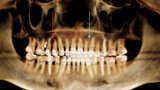

New Age orthodontics and orthopaedics with temporary anchorage devices